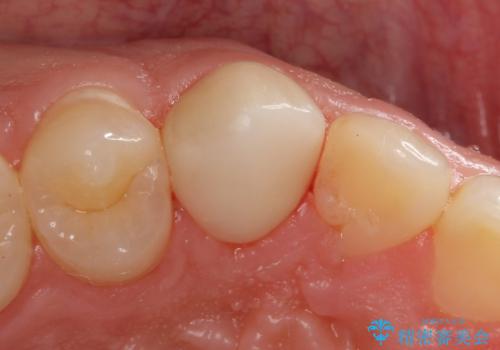

- 右上3 e-maxクラウン 77000円×1本費用は治療当時の料金となります

審美的にも優れるセラミッククラウンで修復し、他の歯も同じ状態になってしまわないよう歯磨き指導をさせていただきました。

穴が開いてしまうと再石灰化は期待できず、歯を削ることでしか対応ができなくなります。

もし気になる変化があれば、事態が悪化する前にお気軽にご相談ください。